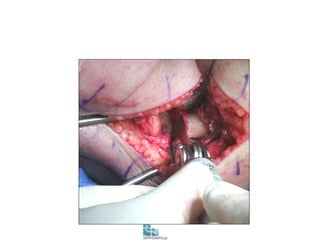

Μετατραυματική αρθρίτιδα αγκώνα

• Αρθροσκοπικό release

• Ανοικτό release

Πρ. Βραχιονιος μ. Πρόσθιος θυλακος

Τρικέφαλοςm.

Posterior

Capsule

Darlis & Sotereanos, J Shoulder Elbow Surg, 2006

Πρόσθιος

θύλακος

Κορωνοειδής

Capitellum

Κεφαλή

κερκίδας

Προσθία τομή

Οπίσθια

τομή

Ωλέκρανο